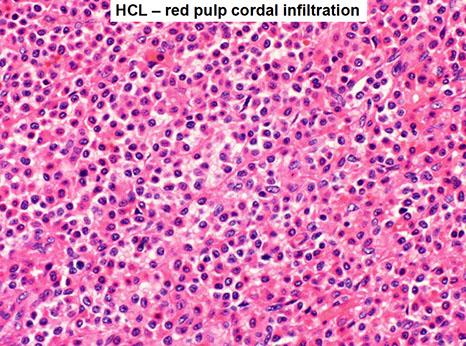

Tissue shows "fried egg" morphology, reticulin fibrosis, blood lakes, mast cells frequent

- Spleen white pulp is atrophic/absent c red pulp cords infiltrated c tumors that blocks circulation

In spleen, see BLOOD LAKES